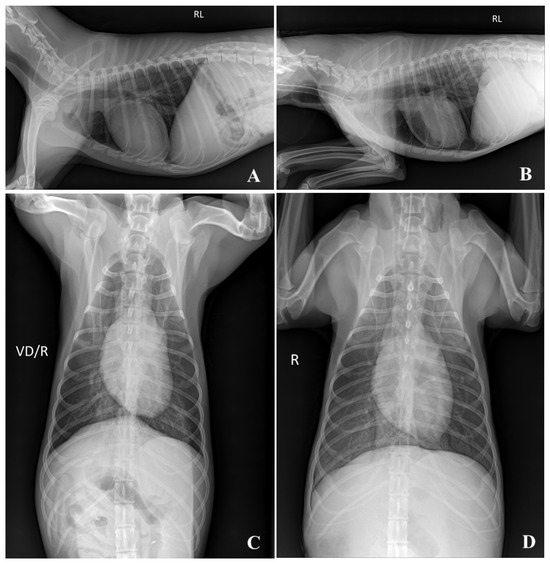

Plain radiography is preferred because it can quickly determine the skeletal structure and retention of gases and liquids in the lungs and digestive organs. In plain radiographic images, all embalming solutions scored >1.3, although the image quality of the TS was the lowest. When intubation with an endotracheal tube was performed to assess whether the lungs had remained inflated, the thoracic cavity was maintained at maximal inflation (Figure 7). However, FS cadavers are difficult to position because of their hard skin and joint tissues [18,22]. The joint flexibility of the TS cadaver makes radiography easier [25]. Creating flexed and extended positions in axial and appendicular joint images is hypothesized to be useful for training.

Figure 7.

Thoracic radiographic images of the FS embalmed cadaver. Fixed as maximal inflated lung condition with intubation of the endotracheal tube. (A,C) = pre-imaging; (B,D) = 12 weeks. RL: Right lateral recumbency; VD/R: Ventodorsal recumbency/Right; R:Right. The mean score of imaging quality was 3.00 for Pre and 2.50 for 12 weeks.